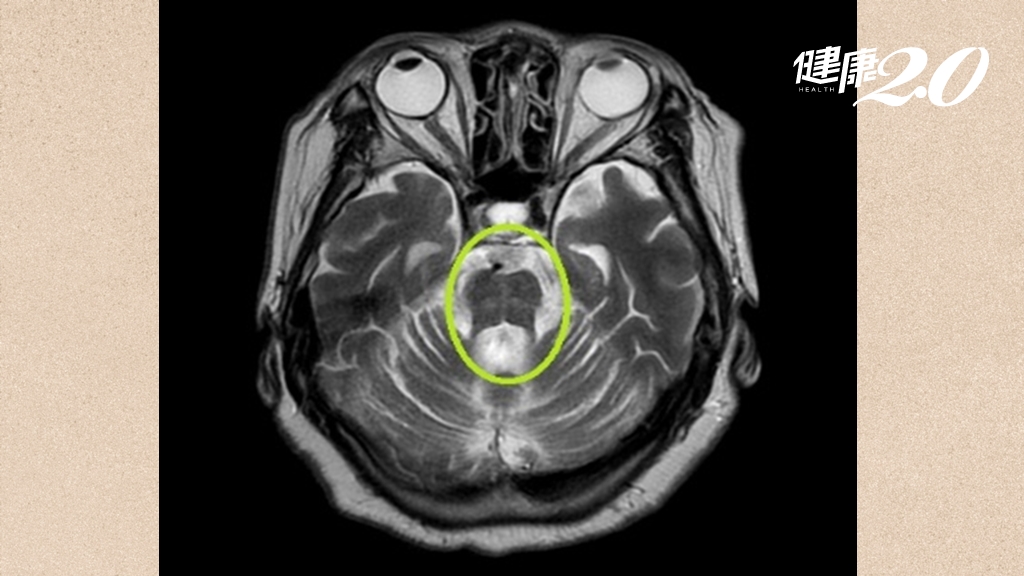

要治療老年憂鬱症,陳文瑩表示,適合的藥物搭配心理治療對於輕、中度的老年憂鬱症患者療效很好,不比年輕的憂鬱症患者差,難治型的老年憂鬱症會使用「重複經顱磁刺激(rTMS)」,以微電流刺激主管情緒的大腦區域的血流、調控情緒迴路的活性,無侵入性,也不需麻醉,可以達成顯著療效。